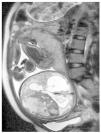

Fig. 3.